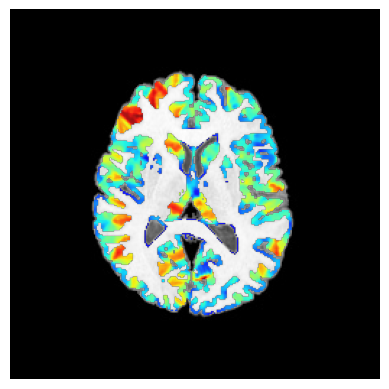

stderr 2025-11-10T00:50:59.619948:*+ WARNING: If you are performing spatial transformations on an oblique dset,

251110-00:50:59,620 nipype.interface INFO:

stderr 2025-11-10T00:50:59.619948: such as ds001226/sub-CON02/ses-preop/anat/sub-CON02_ses-preop_T1w.nii.gz,

251110-00:50:59,621 nipype.interface INFO: